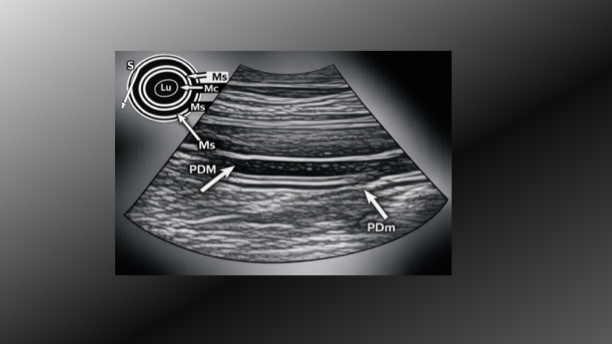

Aquí encontrarás imágenes detalladas que ilustran exploración de órganos abdominales sanos y con patologías en perros y gatos.

Aprende los fundamentos para interpretar imágenes ecográficas de órganos abdominales.